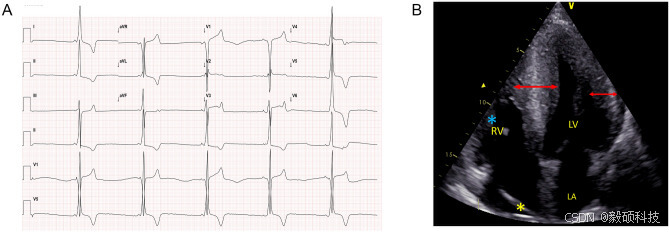

研究组还对样本进行临床和遗传学评估。发现所有患者的 NYHA 心功能分级均为 I 级或 II 级;17 名患者的心电图显示为 WPW 模式(即沃尔夫-帕金森-怀特(Wolff-Parkinson-White)综合征,是一种心脏电生理异常,其特点在于心脏的传导系统存在额外的旁路或异常通路)。全部 22 名患者的心电图平均 PR 间期持续时间为 104 ± 18 毫秒;

图4 PRKAG2 心肌病患者的典型心电图和超声心动图